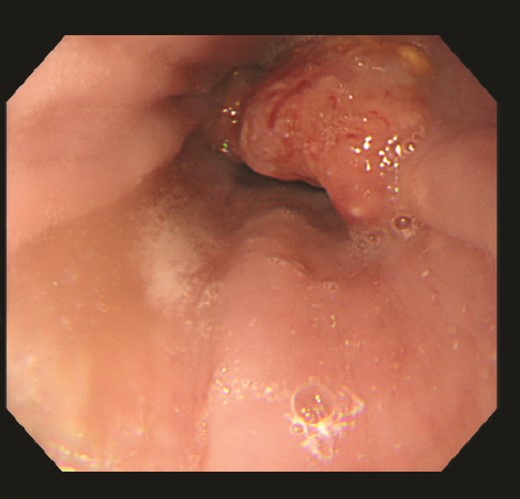

The patient is a 79-year-old woman, complaining of dysphagia, who came to our department after a CT scan with an abnormality in the lower esophagus. Type 3 tumor was found at the EGJ (Fig. 1). Biopsy results showed that the surface of the tumor was covered with non-neoplastic squamous epithelium, and the area directly below the squamous epithelium was occupied by a squamous cell carcinoma component and an adenocarcinoma-like component. Based on TNM classification, it was cT3 cN2 M0 cStageIII. The patient underwent thoracoscopic subtotal esophagectomy and 2-region dissection with a diagnosis of advanced EGJ cancer. The patient was discharged from the hospital 17 days after surgery.

Upper gastrointestinal endoscopy revealed a type 3 esophagogastric junction tumor that had invaded the esophagus by 2 cm. Endoscopically, the neck of the tumor was located at the junction, and together with the histopathologic results, a diagnosis of Siewert type 2 esophagogastric junction carcinoma was made. Initially, a squamous cell carcinoma component and an adenocarcinoma component were observed, and the patient was suspected of having basal cell carcinoma.